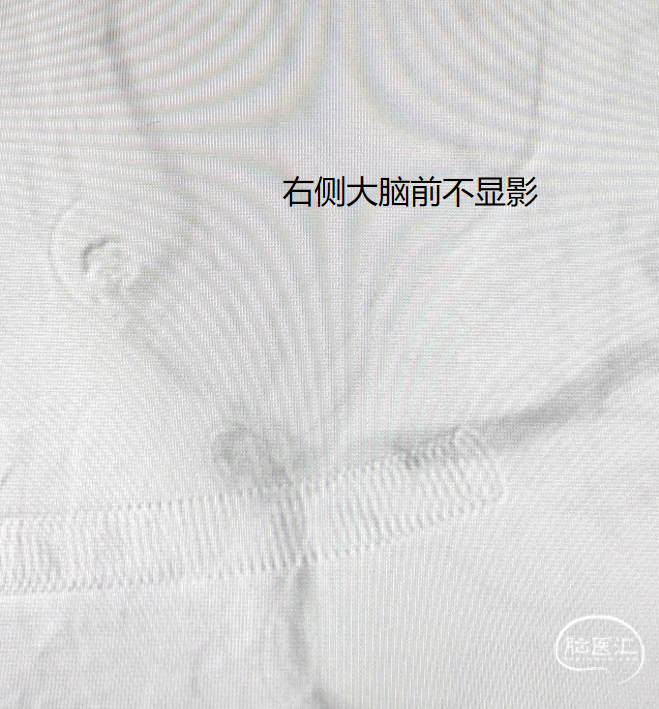

患者右侧大脑前发育纤细;后循环血管无明显异常。

造影见对侧大脑前显影稍差,考虑瘤颈处血栓形成;遂给予静脉团注10ml替罗非班(0.05mg/ml),同时以5ml/h静脉泵注。

造影见对侧大脑前血流恢复,远端瘤体已致密栓塞,但近端瘤体存在残留;